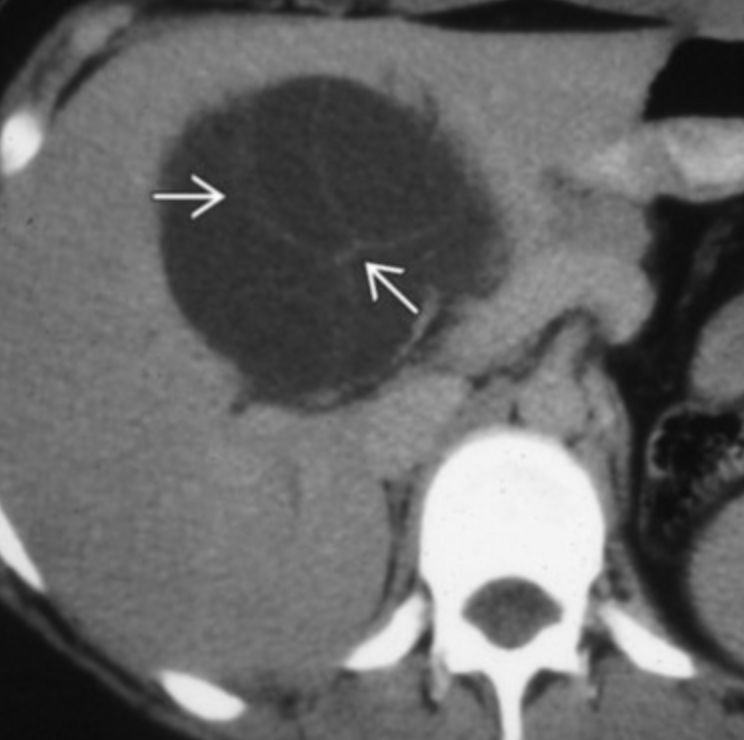

Biliary Cystadenocarcinoma

• Multiseptate liver mass

• Proteinacous fluid content better seen on MR than CT (see different signal on MR not seen on CT basically)

• Cannot really be differentiated fro biliary cystadenoma on imaging alone

• Nodularity of septa suggests malignancy